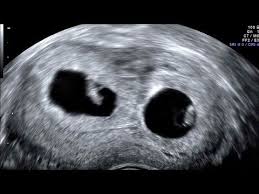

The exact time twins can be detected depends on the type of twins, for example, if they're identical (from one egg) or not. By eight weeks of your twin pregnancy, your babies will have buds for limbs that look like little paddles. Mehr als 200.000 maschinen sofort verfügbar. Most doctors will schedule an ultrasound somewhere between 6 and 10 weeks of pregnancy to confirm the pregnancy and check for multiples. Six full weeks is when you're 6+0 weeks pregnant. I should be 7 weeks, 4 days according to last period. (florida) i suspected i had twins because my beta numbers were high, i had two big follicles during my iui and i'm already big for less than 7 weeks! Seeing twins at 6 weeks is definitely possible. Besides ultrasound at 4 weeks, there are several changes during pregnancy for moms to expect. By four weeks, twins will start showing during ultrasound in form of 2 gestational sacs, but you cannot get clear indication of twins until 6 weeks. The first time i spotted but the other two were gushes. This was taken at 4 weeks 6 days. Some women would rather not know until both twins are relatively safe, while others want to know even if the chances of losing one twin are high.

We had the wonderful opportunity to see our baby's heart flickering on the screen!!! They said the doctor will call me and they may book an ultrasound in another two weeks. By four weeks, twins will start showing during ultrasound in form of 2 gestational sacs, but you cannot get clear indication of twins until 6 weeks. The ultrasound image is of twins at 4 weeks. No fetal heartbeat detectable at 5 weeks 6 days ultrasound.

Between 5 ½ to 6 ½ weeks, a fetal pole or even a fetal heartbeat may be detected by vaginal ultrasound. In this 7th week of pregnancy, your baby's lungs are starting to develop. The ultrasound picture above is of identical twins who share a placenta at 6+2 weeks. Beauty points sammeln & mit der douglas beauty card von exklusiven vorteilen profitieren. This begins with a small lung bud branching out from the upper part of the tube (esophagus) between your baby's mouth. Get to know what you need to take care of when 4 weeks and 6 days pregnant pregnant. I've been posting in october 2012 since i found out i was pregnant in february. You have approximately a 3.35 chance of having twins naturally , without the help of any fertility treatments. They said the baby looked small and measured about 6 weeks. 4 weeks) between 5 ½ to 6 ½ weeks, a fetal pole or even a fetal heartbeat may be detected by vaginal ultrasound. Little arms and legs sprout. You don't hear heartbeats any earlier or later with twins, that i know of. Mehr als 200.000 maschinen sofort verfügbar.